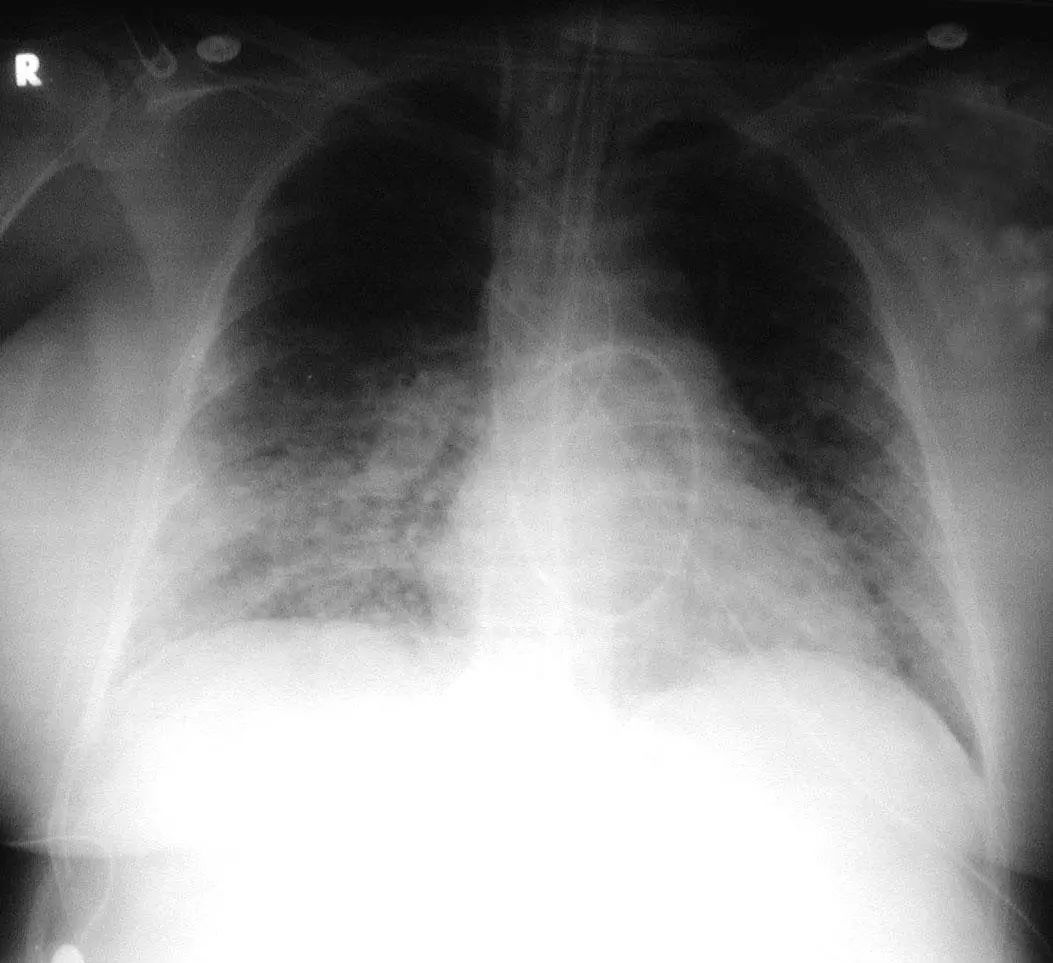

图1.3 细菌性肺炎。早期右肺中叶肺炎的影像学表现。

图1.4 53岁的严重军团菌肺炎患者。胸片显示双肺下叶致密实变。